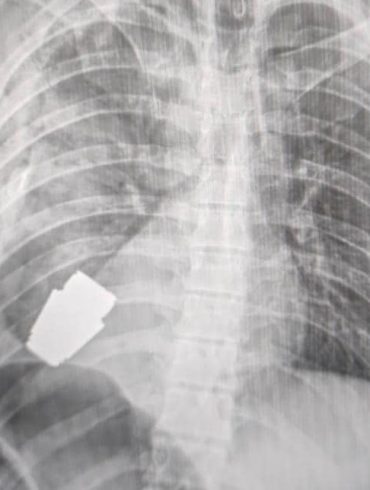

Про це повідомляє Командування Медичних сил ЗСУ на своїй сторінці у Фейсбук. З тіла військовослужбовця видалено гранату від ВОГ, яка...